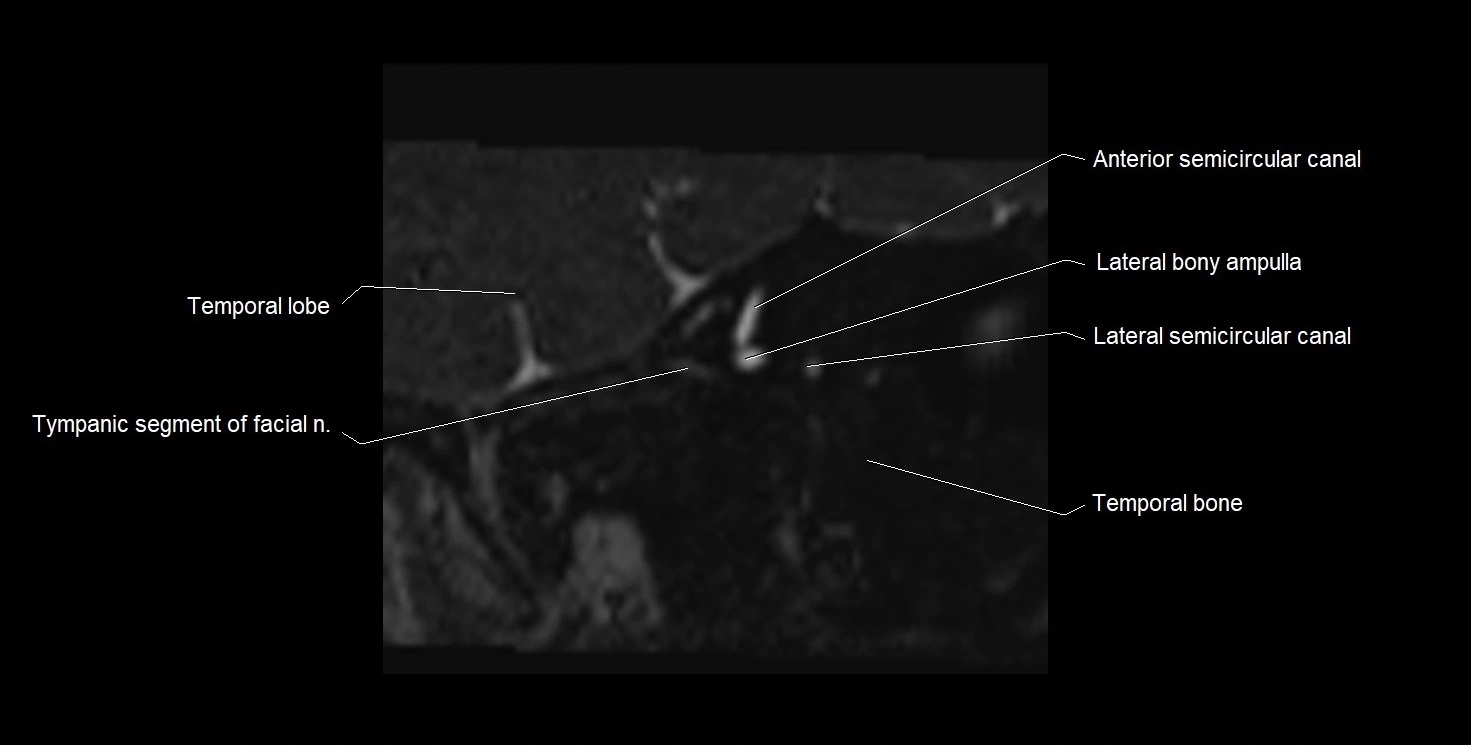

image